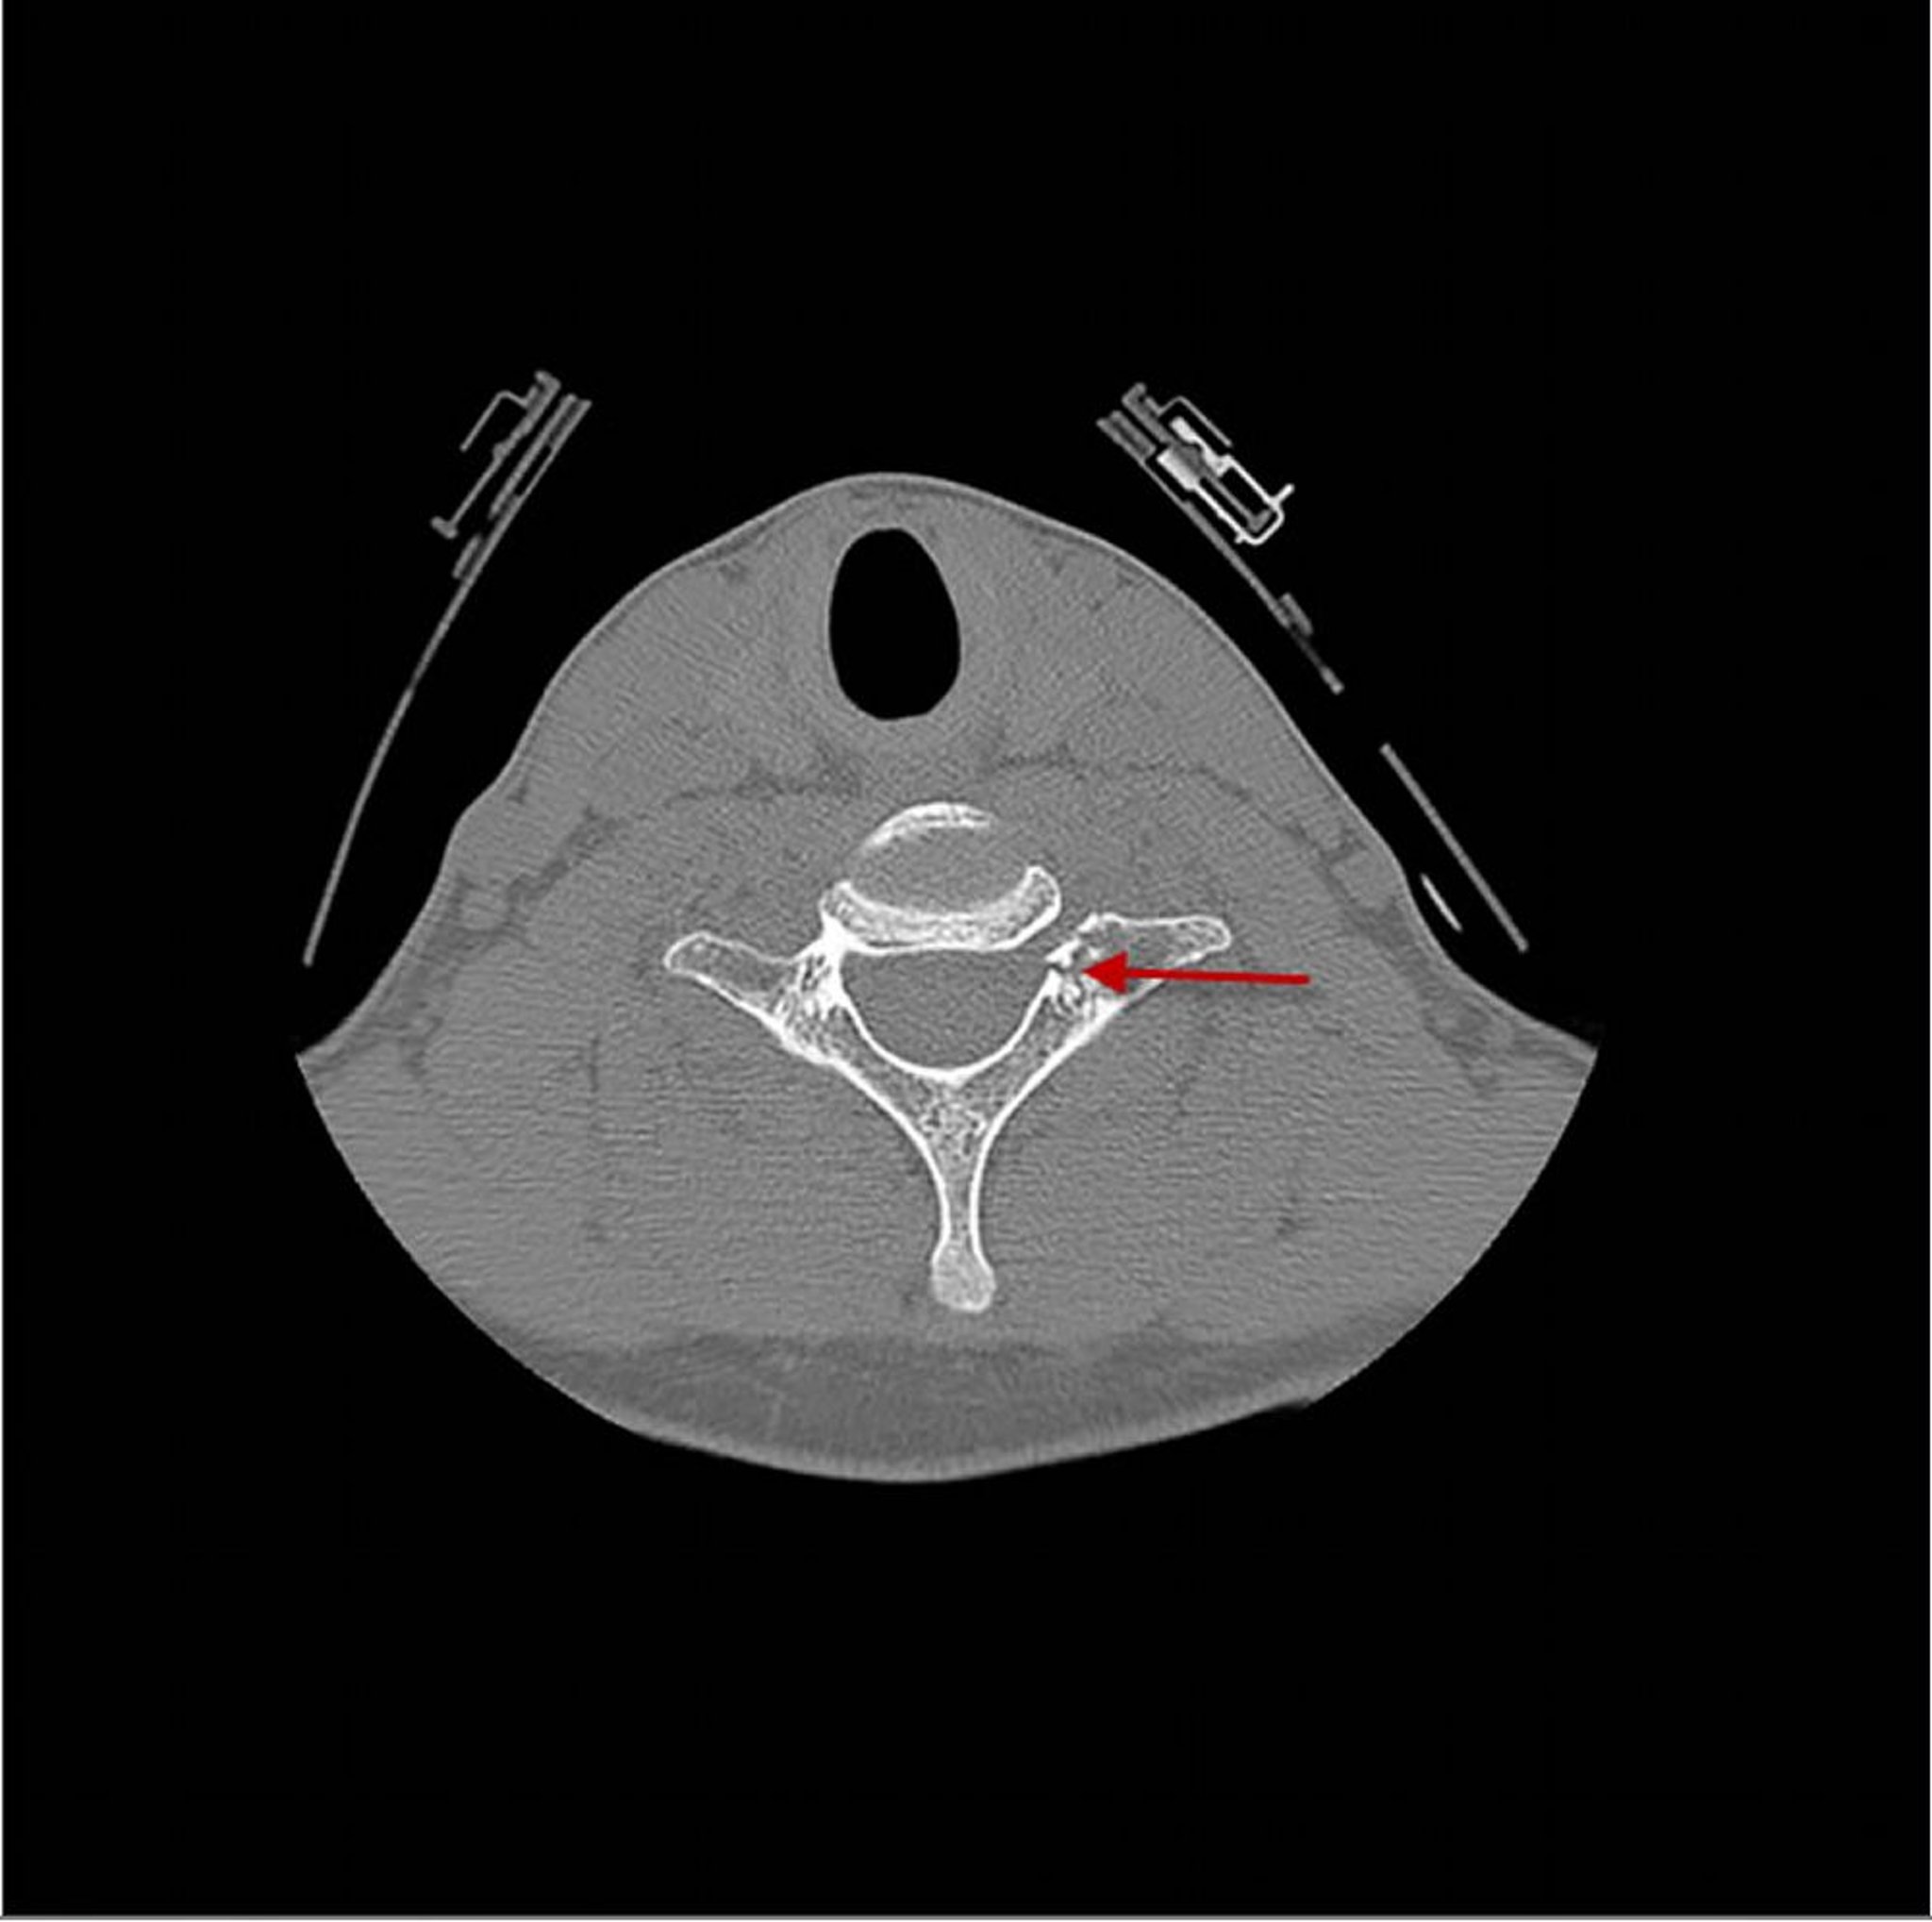

Vertèbre cervicale fracturée

Cette TDM montre une fracture (flèche) de la 7e vertèbre cervicale juste en arrière du corps vertébral.